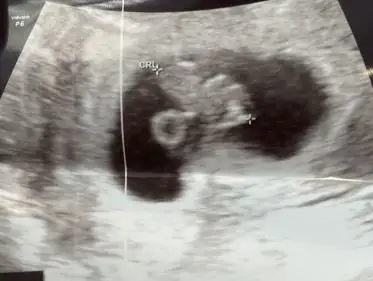

5 ve 14. haftaya kadar olan ultrason fotolarınızı paylaşın. Vajinadan mı yoksa karından mı çekildiğini ve kaç haftalık olduğunu da mutlaka belirtin.